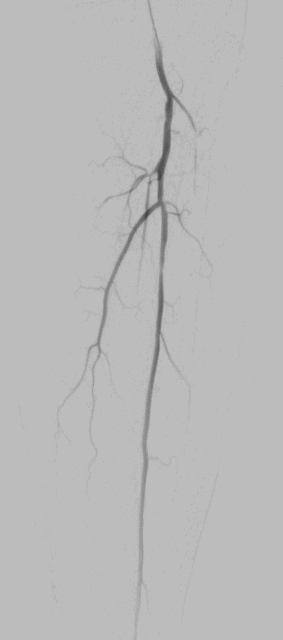

手术过程(一):右侧股动脉穿刺,全身肝素化后,猪尾导管翻山,更换6F长鞘,使用雅培Command-18导丝真腔通过病变,雅培Armada-18 4mm×120mm球囊预扩张,造影提示广泛夹层,植入雅培Supera 5mm×120mm跨关节支架,并使用雅培Armada-18 5mm×120mm球囊后扩张

图片

支架植入后造影